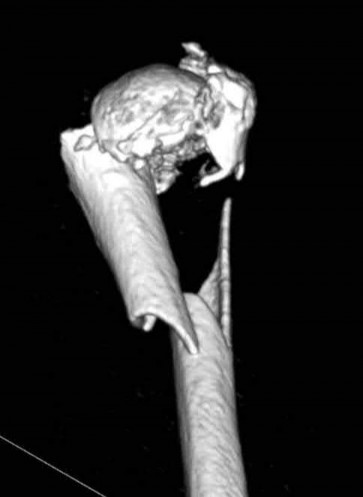

A 70-year-old woman falls down a flight of stairs and sustains the injury shown in Figures A and B to her dominant upper extremity. She lives alone and has no other medical history. Which of the following surgical options is best to minimize complications for this fracture pattern?

This patient has a complex proximal humerus fracture with metaphyseal comminution and poor bone stock. Cemented reverse total shoulder arthroplasty (rTSA) using a long stem prosthesis and tuberosity repair is indicated.

Proximal humerus fragility fractures are hard to treat because of comminution and poor bone stock. AVN is common with glenohumeral fracture-dislocation. Hemiarthroplasty (and standard total shoulder arthroplasty, TSA) is unreliable because of dependence on tuberosity healing. rTSA is recommended for fractures in patients >70 years with severely comminuted fractures, high likelihood of head AVN, and poor tuberosity bone quality (osteoporosis or comminution).

Bufquin et al. retrospectively reviewed the use of rTSA for treatment of 43 patients with 3- and 4-part proximal humerus fractures. They found satisfactory elevation (97°), ER in abduction (30°), constant scores (44) and modified Constant scores (66%). Complications included calcification (90%), tuberosity displacement (53%) and scapular notching (25%). They concluded that rTSA was a good procedure because it provides pain relief and easier functional recovery in spite of failed tuberosity healing.

Anakwenze et al. systematically reviewed acute proximal humerus fractures. Frequency weighted range of motion was flexion 122°, abduction 97°, ER at neutral 18°. Tuberosity repair yielded higher ER compared to no repair.

Scapular notching was the most common complication (32%). They concluded that rTSA patients tended to be elderly women with 4-part fractures, had good pain control but residual dysfunction.

Jobin et al. reviewed rTSA for management of proximal humerus 3- and 4-part fractures. They note >50% of cases have tuberosity resorption. They recommend repairing the greater tuberosity to restore infraspinatus/teres minor function which improves external rotation strength. Greater tuberosity malunion is not a result of secondary displacement, but rather, from intraoperative malreduction. Lesser tuberosity repair should be performed if there is significant bone loss or intraoperative anterior instability.

Figures A and B are AP radiograph and 3D reformatted CT scan showing comminuted proximal humerus fracture dislocation. Illustration A shows rTSA performed with distal cementation of a long stem prosthesis and cerclage fixation of the proximal shaft and the tuberosity fragments.